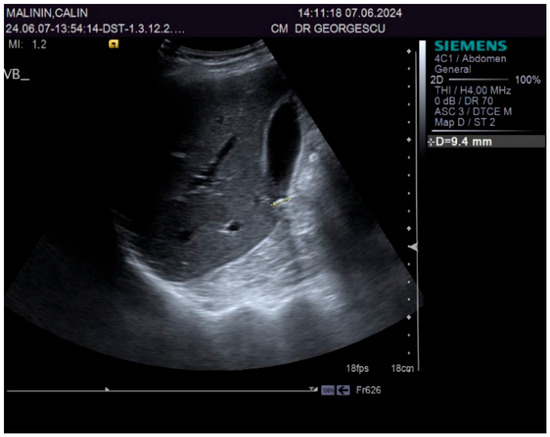

Figure 2.

Ultrasound aspect: diffuse liver steatosis.

A 55-year-old male patient, complaining of recently onset, persistent generalized itching, was first examined by a dermatologist in the middle of May 2024 and no physical signs of skin disorder were found. Routine blood and stool workups were performed. No food or respiratory allergies were identified, and stool samples were negative for parasites. The recommended antihistamines were only partially effective, pruritus being present even during nights, resulting in a lowering of the patient’s quality of life. Given the mild dyspeptic-associated complaints, the patient was referred to a gastroenterological consultation on 7 June 2024 with a suspected biliary disorder. Medical history revealed no significant familial or personal pathologies, no smoking or alcohol drinking and no exposure to toxic substances. Physical examination found no particular pathological features, no peripheral palpable lymph nodes or skin lesions, normal respiratory and cardiovascular aspects, and blood pressure = 120/70 mmHg. However, the patient was overweight (BMI = 28 kg/m2) and displayed a mild palpatory tenderness of the middle and upper-right abdominal quadrant. Abdominal duplex ultrasound revealed multiple small echogenic formations adjacent to the gallbladder wall, likely cholesterol polyps. As illustrated in Figure 1 and Figure 2, two small calculi were also visualized in the infundibular zone. No biliary tree dilation was observed. Additional findings included mild liver steatosis, thickening of the stomach and duodenal walls, and a hyperechoic pancreatic texture. Aortic ectasia (2.7 cm in diameter) was noted just proximal to the distal bifurcation. No ascites or retroperitoneal lymph nodes were present.